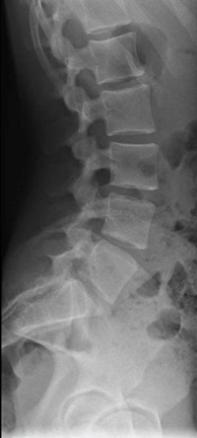

Les radiographies réalisées ne révèlent aucune anomalie (fig. 1). Le scanner demandé secondairement montre une lyse isthmique bilatérale en L3 prédominant à gauche (fig. 2).

L’examen complémentaire de base est la radiographie standard du rachis lombaire de face, de profil et de trois quarts, mais elle ne permet pas toujours de poser le diagnostic. Ainsi, en cas de normalité du bilan radiographique, mais d’un interrogatoire et d’un examen clinique évocateurs, le recours à la tomodensitométrie est nécessaire.